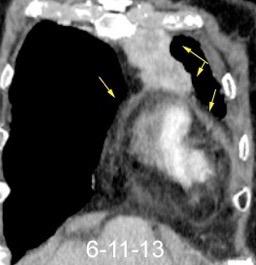

102. HEMATOMA MEDIASTÍNICO.

Hematoma retroesternal y pericárdico en cirugía de válvula mitral. Migración de suturas